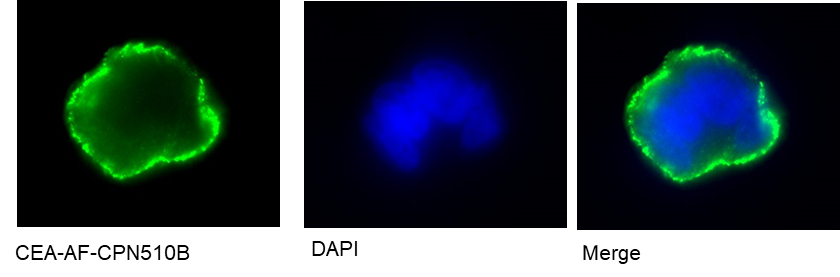

CPN 510B linked to anti-carcinoembryonic antigen (CEA) affimer targeting colorectal cancer cells, imaged by the University of Leeds

Shortwave carbon nanotubes have potential applications in photothermal cancer therapies, so we've got the potential to look further down the line at a CPN particle with an antibody to target a tumor cell. If you excite it at the correct IR wavelength, (because it's infrared, it'll penetrate the tissue), you can kill it with heat instead of chemotherapy.